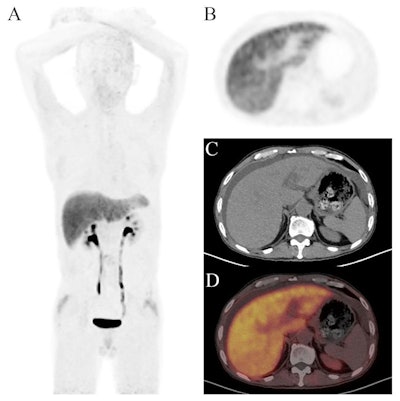

Images of a 55-year-old man with a 10-year history of hepatitis B virus infection. He presented with abdominal distension and yellowing of the skin and sclera for six months. The maximum intensity projection (MIP) image of Ga-68 FAPI-PET/CT showed diffuse tracer uptake in the liver region. Axial images showed significant liver uptake with abdominal effusion (SUVmean = 3.13; TBRliver-to-blood = 2.84; TLfap = 41.3). F4 level of liver fibrosis was confirmed by liver biopsy.Images of a 55-year-old man with a 10-year history of hepatitis B virus infection. He presented with abdominal distension and yellowing of the skin and sclera for six months. The maximum intensity projection (MIP) image of Ga-68 FAPI-PET/CT showed diffuse tracer uptake in the liver region. Axial images showed significant liver uptake with abdominal effusion (SUVmean = 3.13; TBRliver-to-blood = 2.84; TLfap = 41.3). F4 level of liver fibrosis was confirmed by liver biopsy.Scientific ReportsAccording to the results, Ga-68 FAPI-04 PET/CT yielded a sensitivity of 87.5%, specificity of 83.3%, and PPV of 87.5%. Both FIB-4 and Fibroscan correctly classified 10 out of 14 (71.4%) participants, while Ga-68 FAPI-04 PET/CT successfully differentiated 12 of 14 (85.7%) participants (weighted kappa = 0.841).